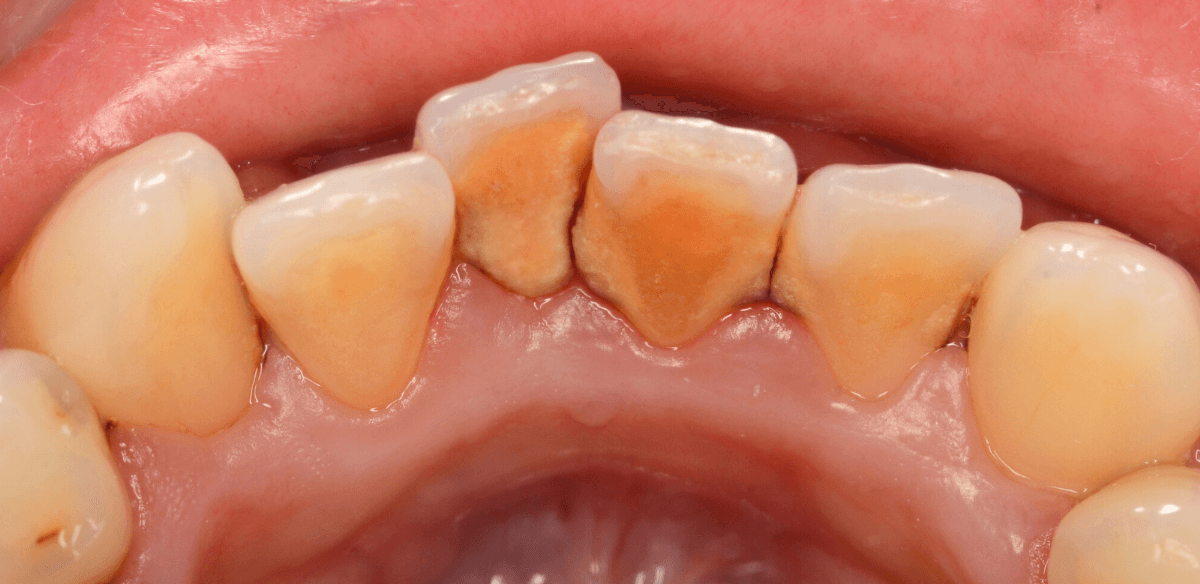

Case.4「歯の周りの黒い物を取って欲しい」という患者さん

今回は、「歯の周りの黒い物を取ってほしい」という訴えの患者さんのケースです。

着色かな、と思い口の中を拝見すると、歯の表面まで露出した縁下歯石でした。

当院は、(現在のところ)比較的若い患者さんが多いので、ここまでハッキリ縁下歯石が露出しているケースは珍しいです。

患者さんには、歯周病の基本的な説明とブラッシング指導をした後、まず下の歯の歯石除去から始めました。

ブラッシング指導・下の前歯の歯石除去直後の写真です。

これだけでも、かなり改善したかと思いますが、これだけの縁下歯石の量ですから、一回の歯石除去で全て取り切れるはずがありません。

根気よく、歯石除去を続ける必要があります。